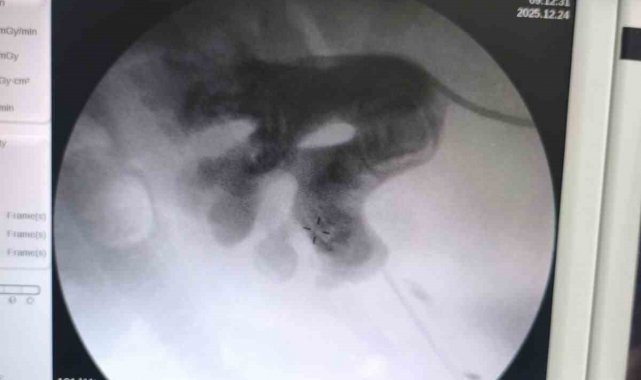

Siirt'te 34 yaşındaki Fatih Aslan, ateş, üşüme ve idrar yaparken yanma şikayetleriyle hastaneye başvurdu. Yapılan muayene ve testlerin ardından piyelonefrit (böbrek iltihabı) tanısı konuldu ve enfeksiyon tedavisi tamamlandı. Üroloji uzmanı doktor Miraç Ataman, gerçekleştirilen operasyon, hem tıbbi açıdan hem de toplumsal sağlık açısından önemli bir başarı olduğunu söyledi. Ataman, "34 yaşındaki erkek hastamız, ateş, üşüme ve idrar yaparken yanma şikayetleri ile acil servise başvurdu. Yapılan değerlendirme sonucunda piyelonefrit (böbrek iltihabı) tanısı konuldu ve yatış yapılarak enfeksiyon tedavisi başarıyla tamamlandı. Tanı sürecinde yapılan Bilgisayarlı Tomografi (BT) görüntülemesinde böbreğin tamamını kaplayan, sert yapıda(950-1450 HU), literatürde staghorn olarak adlandırılan ve halk arasında ' geyik boynuzu taşı ' diye bilinen büyük taş saptandı. Staghorn taşlar böbreğin tüm boşluklarını doldurup, tekrarlayan enfeksiyonlara ve uzun vadede böbrek fonksiyon kaybına yol açabildiğinden tedavisi hayati önem taşımaktadır. Biz de bu vakamızda, Perkütan Nefrolitotomi (PCNL) yöntemiyle böbreğe küçük bir cilt kesisi üzerinden girerek endoskopik cihazlarla taşları parçalayıp çıkardık. PCNL, özellikle çapı 2 cm'den büyük ve kompleks taşlarda altın standart kabul edilmektedir. Normalde staghorn taşların temizlenmesi uzun süren ve çoğu zaman birden fazla seans gerektiren zorlu bir süreçtir. Modern altyapısı sayesinde, ciltten tek giriş yolu açılarak yaklaşık 1,5 saatlik bir seansta böbreğin tüm taş yükü başarıyla temizlendi" dedi.